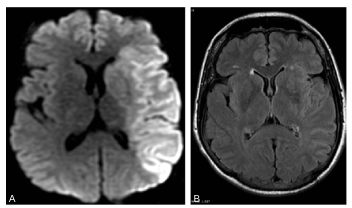

En IRM, l’ischémie cérébrale est visible dès la première heure sur les séquences de diffusion sous l’aspect d’un hypersignal correspondant à un territoire vasculaire artériel (figure 50.1). Ces anomalies apparaissent plus tardivement (au-delà de 6 heures) sur la séquence T2/FLAIR, ce qui permet de dater les AVC du réveil. L’angiographie par résonance magnétique montre les artères circulantes, alors que l’artère occluse n’est pas visualisée.

Fig. 50.1 Signes d’AVC ischémique en phase aiguë en IRM.

IRM réalisée à 3 heures de l’installation du déficit. La coupe axiale pondérée en diffusion (A) montre très nettement une plage en hypersignal à contours bien limités touchant la substance blanche et la substance grise et correspondant au territoire superficiel et profond de l’artère cérébrale moyenne gauche. Ces anomalies sont à peine visibles sur la séquence FLAIR (B).

Source : CERF, CNEBMN, 2022.